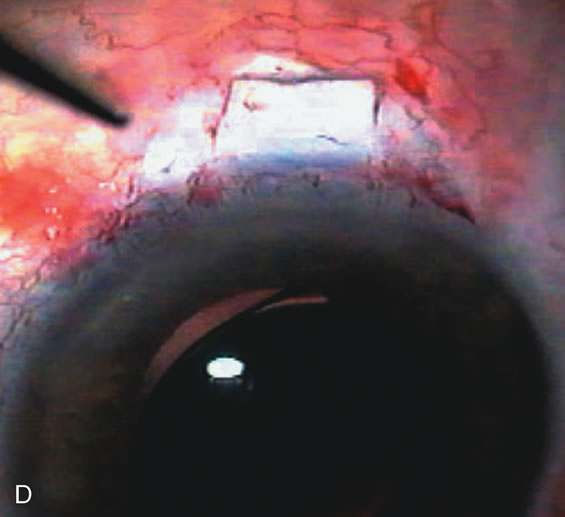

Fig. 4. Viscocanalostomy with deep sclerectomy and phacoemulsification. Nonpenetrating filtration procedures (NPFS) may be combined with phacoemulsification. Patients with mild disc damage and a history of limited topical drug therapy are the best candidates. Patients who require an IOP in the low teens are not good candidates for NPFS. By definition, NPFS is designed to lower IOP without penetrating into the anterior chamber, thereby avoiding the complications associated with trabeculectomy. Viscocanalostomy is intended to allow aqueous to percolate through a trabeculodescemetic membrane into a subscleral cavern created by the deep sclerectomy. The aqueous diffuses from the cavern into the dilated ostia of Schlemm's canal and into the episcleral venous plexus. A. Fashion a uniform 300-micron superficial scleral flap 1 mm into clear cornea. B. Construct a second 600-micron deep flap that facilitates the unroofing of Schlemm's canal, seen as the darker area. C. Use viscoelastic to dilate the ostia of Schlemm's canal. The major problem with viscocanalostomy is the eventual closure of the ostium decreasing flow to the episcleral plexus. D. Dissect the deep flap anteriorly into clear cornea creating the trabeculodescemetic membrane. This membrane is clearly seen between the scleral spur and the bend of the deep flap. The integrity of this membrane ensures the nonpenetrating portion of the surgery. Another problem with NPFS is the eventual fibrosis of this initially transparent membrane requiring goniopuncture. E. Deep sclerectomy gets its name from removal of the deep flap. Removal of this flap creates the potential subscleral space for accumulation of aqueous before it enters Schlemm's canal and exits the episcleral venous plexus. After removal of the deep flap, the superficial flap is sutured into place and conjunctiva closed. Approximately half of these procedures develop a shallow bleb.